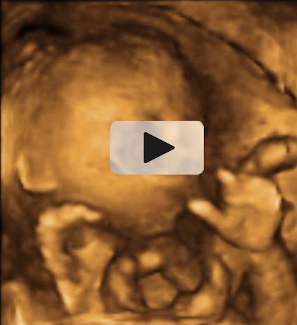

El feto aún se puede mover sin problemas

En la semana 20 de embarazo el bebé aún se mueve libremente dentro del útero materno. Como este feto con la cara de perfil, que se apoya en la pared uterina ayudándose del puño y la nariz. Podemos ver perfectamente la mano cerrada y los dedos, así como los rasgos del perfil y el cráneo.

En esta imagen podemos ver cómo el bebé aún tiene sitio para moverse a sus anchas en el útero durante la semana 20 de gestación.